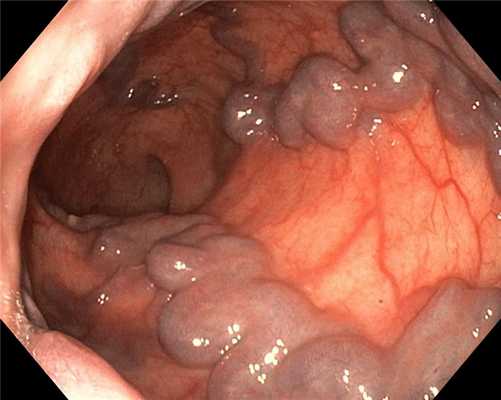

Инвертированное, отечное устье червеобразного отростка в просвет слепой кишки при аппендикулярном инфильтрате